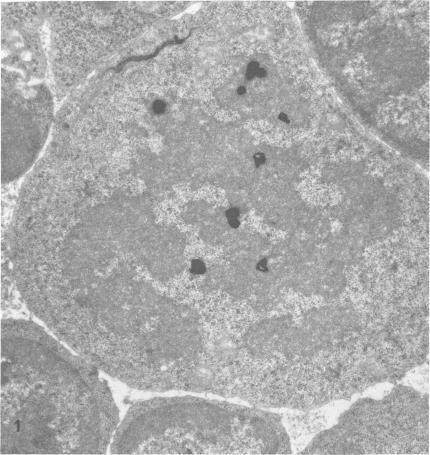

Cellular events during the expression of immunologic memory.

A series of experiments were designed to identify cytologically the cell endowed with immunologic memory and to depict morphologically the cellular events that occurred during the anamnestic response. With the use of radioactive labels and autoradiography at the light and electron microscopic levels, the concatenated phenomena from activation of memory cells to production of antibody could be followed. The memory cell was found to be a lymphocyte which, when activated by specific antigen, enlarged and transformed into either a blast cell or an immature plasma cell. Accompanying this transformation was a boost in proliferative activity of blast and immature plasma cells. This augmented mitotic activity was significantly greater than the level determined in control situations. Following the proliferation among labelled blast and immature cells, maximal labelling occurred in temporal sequence among plasma cells and large lymphocytes and finally among small lymphocytes. Antibody-forming cells were detected chiefly among lymphocytes and plasma cells and increased over the 4 days during which lymphocytes and plasma cells were differentiating from precursor immature elements. The primary response to antigen simulated in many respects the secondary response, but at a significantly lower level.